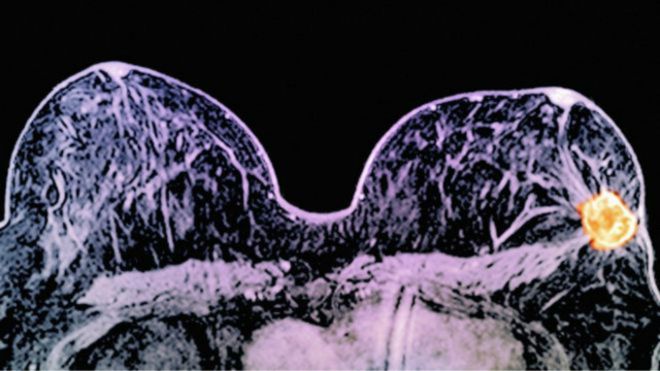

Uma combinação de dois medicamentos pode diminuir muito ou eliminar alguns tipos de câncer de mama em apenas 11 dias, de acordo com médicos britânicos.

O Mutirão de Rastreamento do Câncer de Mama, cujo início estava previsto para a última sexta-feira (04), foi adiado. Segundo a Prefeitura Municipal, “por questões de detalhes na organização”, o Programa de Rastreamento será realizado a partir da segunda quinzena de março.